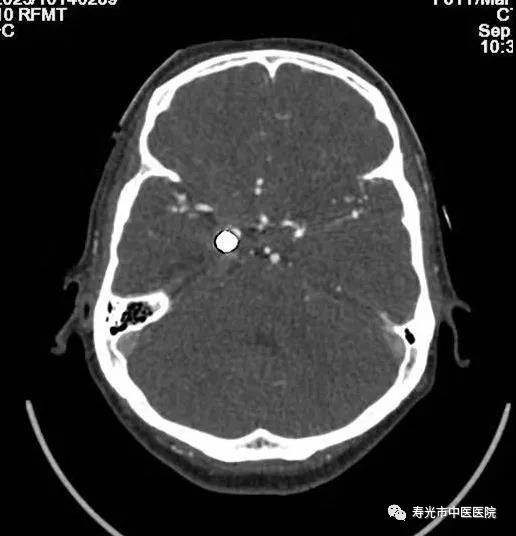

CT检查:清晰成像 挑战重疾

256排Revolution CT被称为“革命型CT”、“CT界的航母”,融合超高端CT的能谱扫描、高时间分辨率扫描和宽体探测器扫描三个领域顶尖科技于一身,实现了无限制1-Beat心脏成像、无限制1-Stop脑卒中成像、多通道主机能谱成像,打造了CT覆盖范围、速度、图像质量、辐射剂量、能谱和扫描舒适性的业界新典范,建立了心血管、神经、肿瘤、呼吸系统、泌尿系统及骨科专业等疾病的成像和低剂量筛查领域全新标准,大幅提高医疗效率和患者体验,有效协助医生进行精准诊断和应对重疾挑战。

如今胸痛病人比较多见,而胸痛确诊需要“排除法”,传统的检查方法是分别做肺动脉、胸主动脉和冠脉的造影,一一排除之后,发现病灶,每次检查都要为患者注射一次对比剂。而使用这台仪器,只需注入一次对比剂,就能完成对这三个部位的检查,实现三联扫。“这给胸痛中心和急性胸痛病症的检查流程改善带来了福音。”

领先之处不仅在此,在做冠脉成像的时候,传统检查需要药物降低患者的心率,使用这台机器,不需要控制心率,只需患者心脏搏动一次,用0.28秒的时间就可以完成。“即使心率不齐的患者,也可以通过这台仪器进行检查。”

去伪影技术更是极大帮助了医生进行治疗。有一位患者,曾经做过脑动脉瘤手术,不久前又出现症状,需要再进行脑血管成像。可是患者脑部已经置入了金属,使用普通CT扫描时,金属会带来反射,排出来的照片一片模糊根本看不清楚病灶。他慕名来到寿光市中医医院求助,在这里,医生利用这台CT的去伪影技术,对他进行了扫描,扫描成像非常清楚。这成了该设备去伪影技术的一个经典病例,美国GE公司的培训师特意将影像搜集去,将在全世界范围进行分享。

CT去伪影扫描效果对比